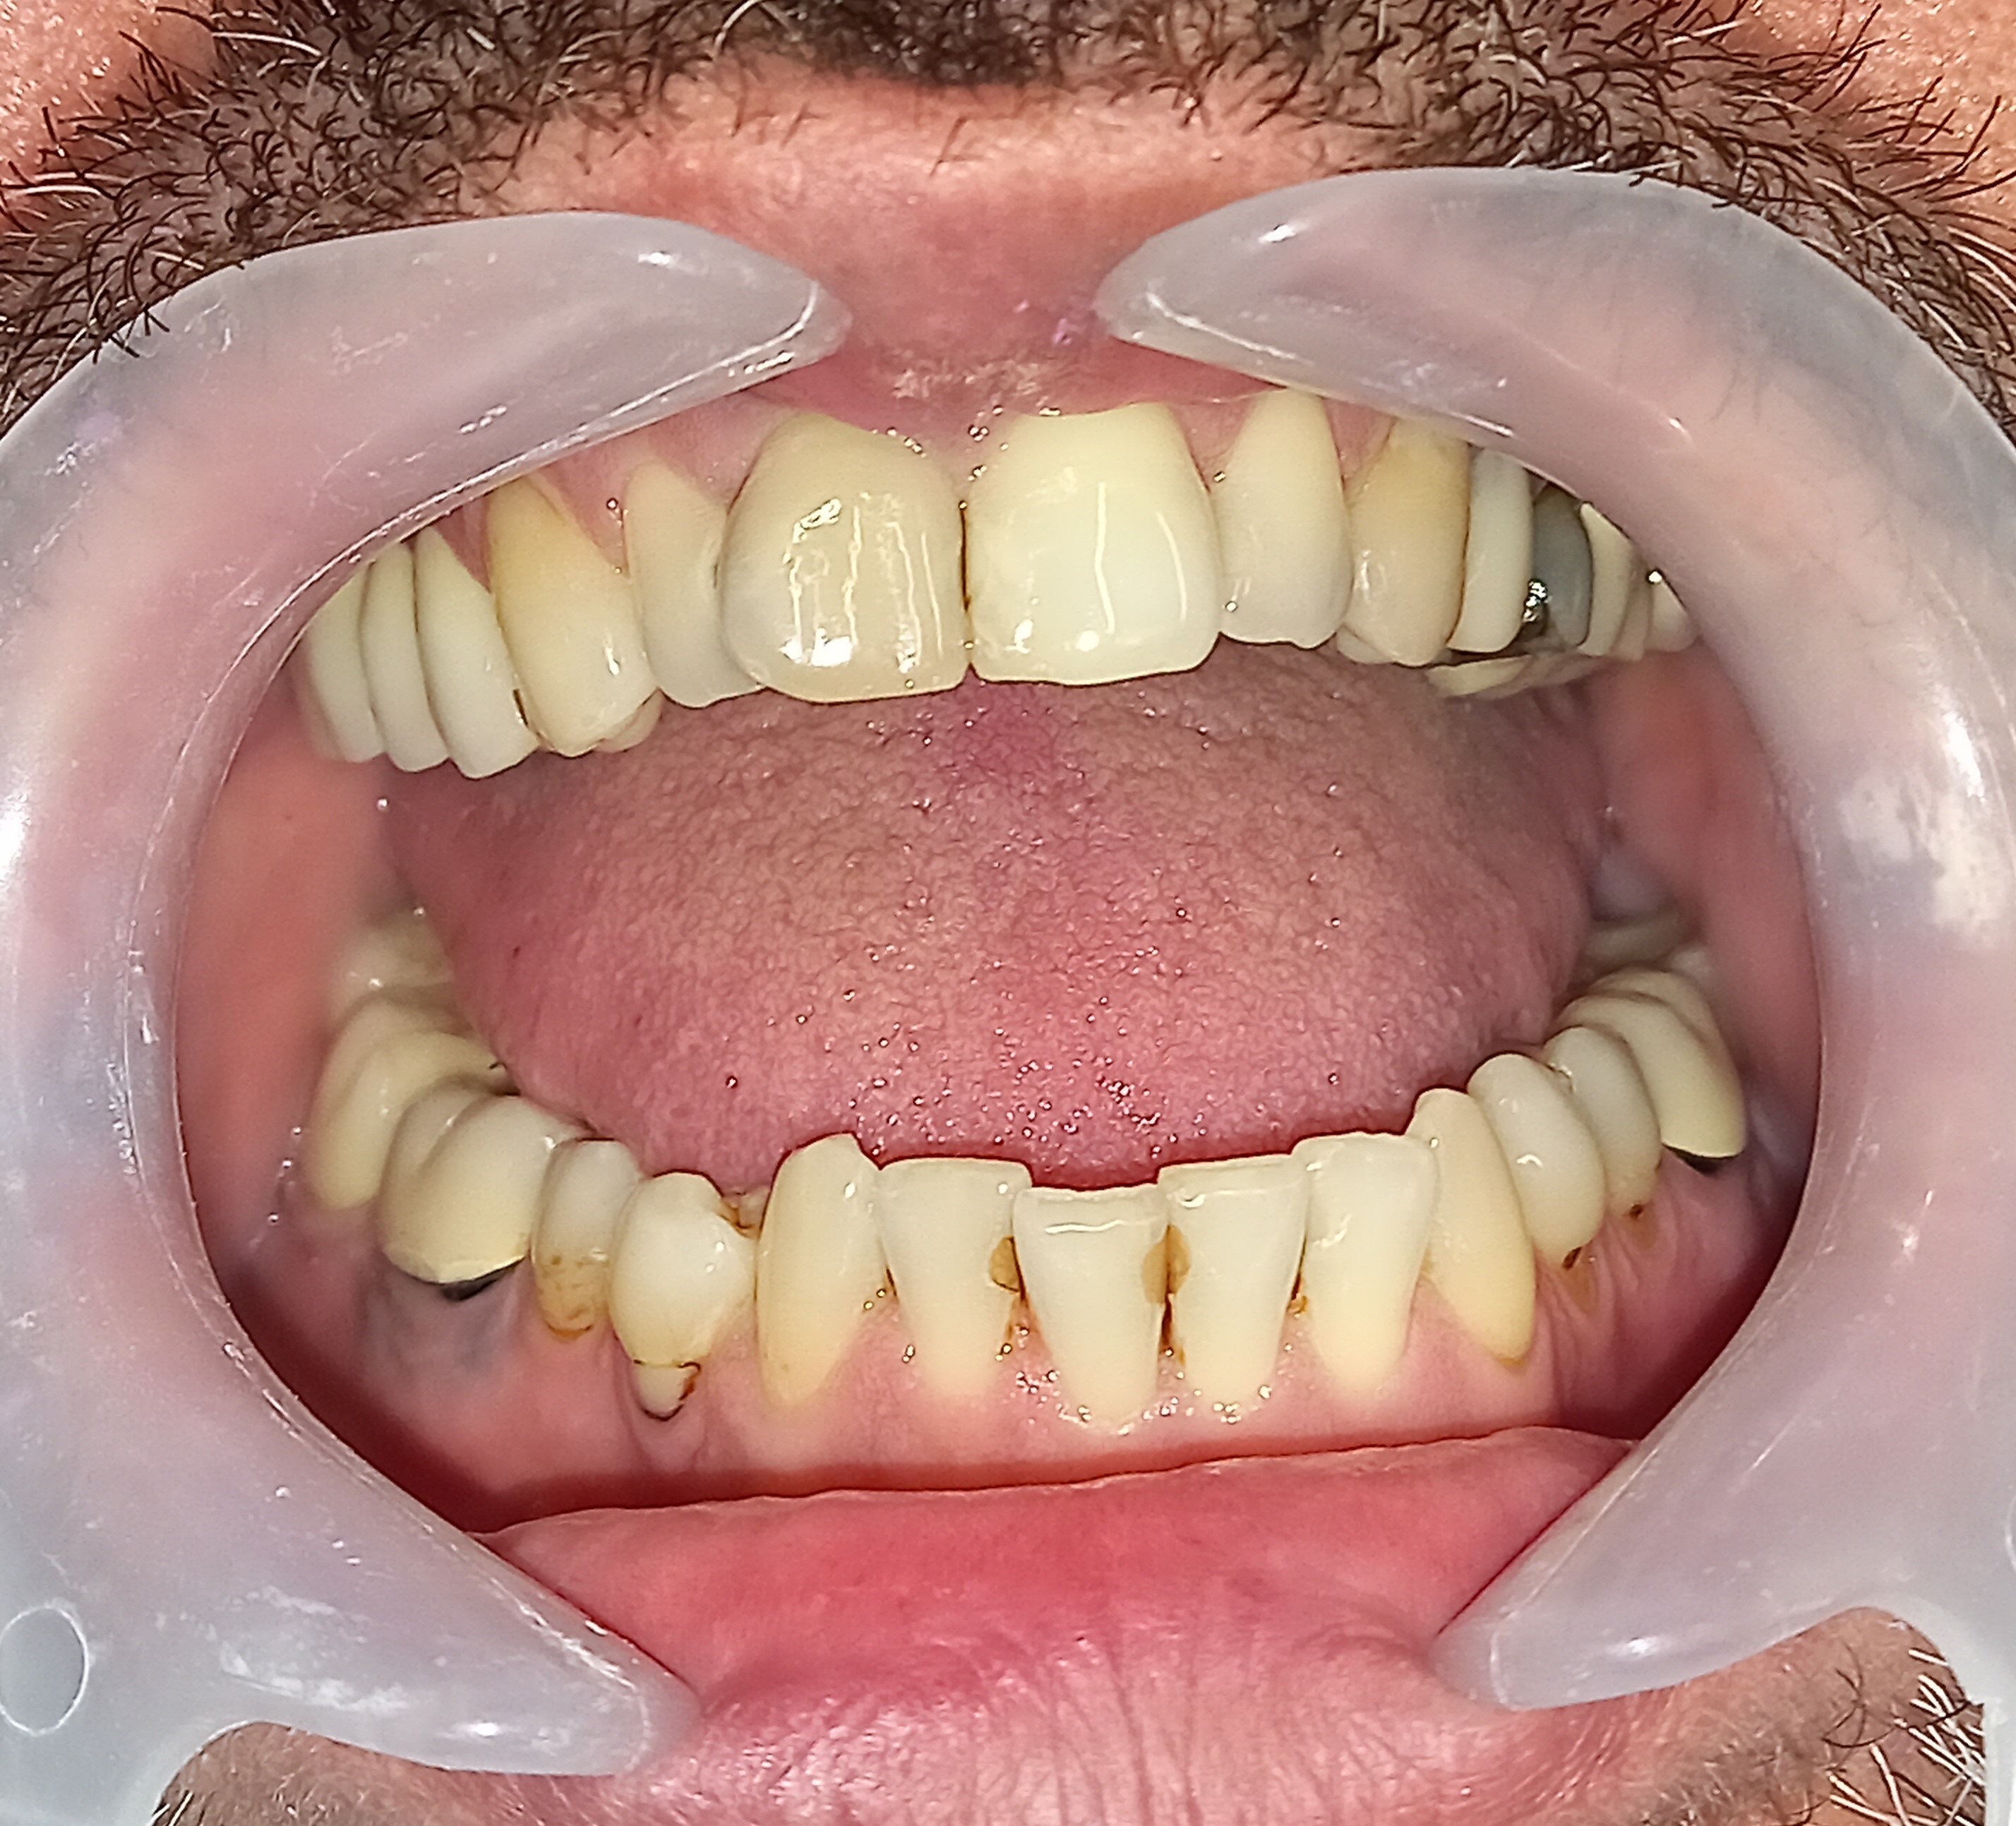

Ο ασθενής είχε πάρα πολλά χρόνια να επισκεφτεί τον οδοντίατρο. Πρόκειται για ένα απαιτητικό περιστατικό, κατά το οποίο ο ασθενής ήταν πολύ συνεργάσιμος καθώς ήθελε να αποκτήσει ένα όμορφο και λαμπερό χαμόγελο. Αρχικά εξάχθηκαν όσα δόντια δεν μπορούσαν να διατηρηθούν πλέον στο στόμα του ασθενή. Στη συνέχεια απονευρώθηκαν τα περισσότερα δόντια και ακολούθησαν ανασυστάσεις όλων των δοντιών. Εφόσον είχε αποκατασταθεί η φλεγμονή των ούλων λήφθηκαν αποτυπώματα και στάλθηκαν στον οδοντοτεχνίτη ο οποίος κατασκεύασε ολοκεραμικές θήκες, οι οποίες ήταν ενωμένες μεταξύ τους (ολοκεραμικό πέταλλο). Ο ασθενής φορούσε προσωρινή γέφυρα στο μεσοδιάστημα που χρειάστηκε ο οδοντοτεχνίτης να κατασκευάσει τη μόνιμη προσθετική εργασία.

Ο ασθενής είναι πολύ χαρούμενος με το λειτουργικό και αισθητικό του αποτέλεσμα. Πρέπει να αναφερθεί οτι όσο καιρό ο ασθενής δεν είχε δόντια δυσκολευόταν πολύ στην άρθρωση του λόγου.

ΠΡΙΝ

Ενδιάμεση κατάσταση αφού ολοκληρώθηκαν οι ανασυστάσεις δοντιών

Ολοκεραμικό πέταλο ζιρκονίου

ΜΕΤΑ